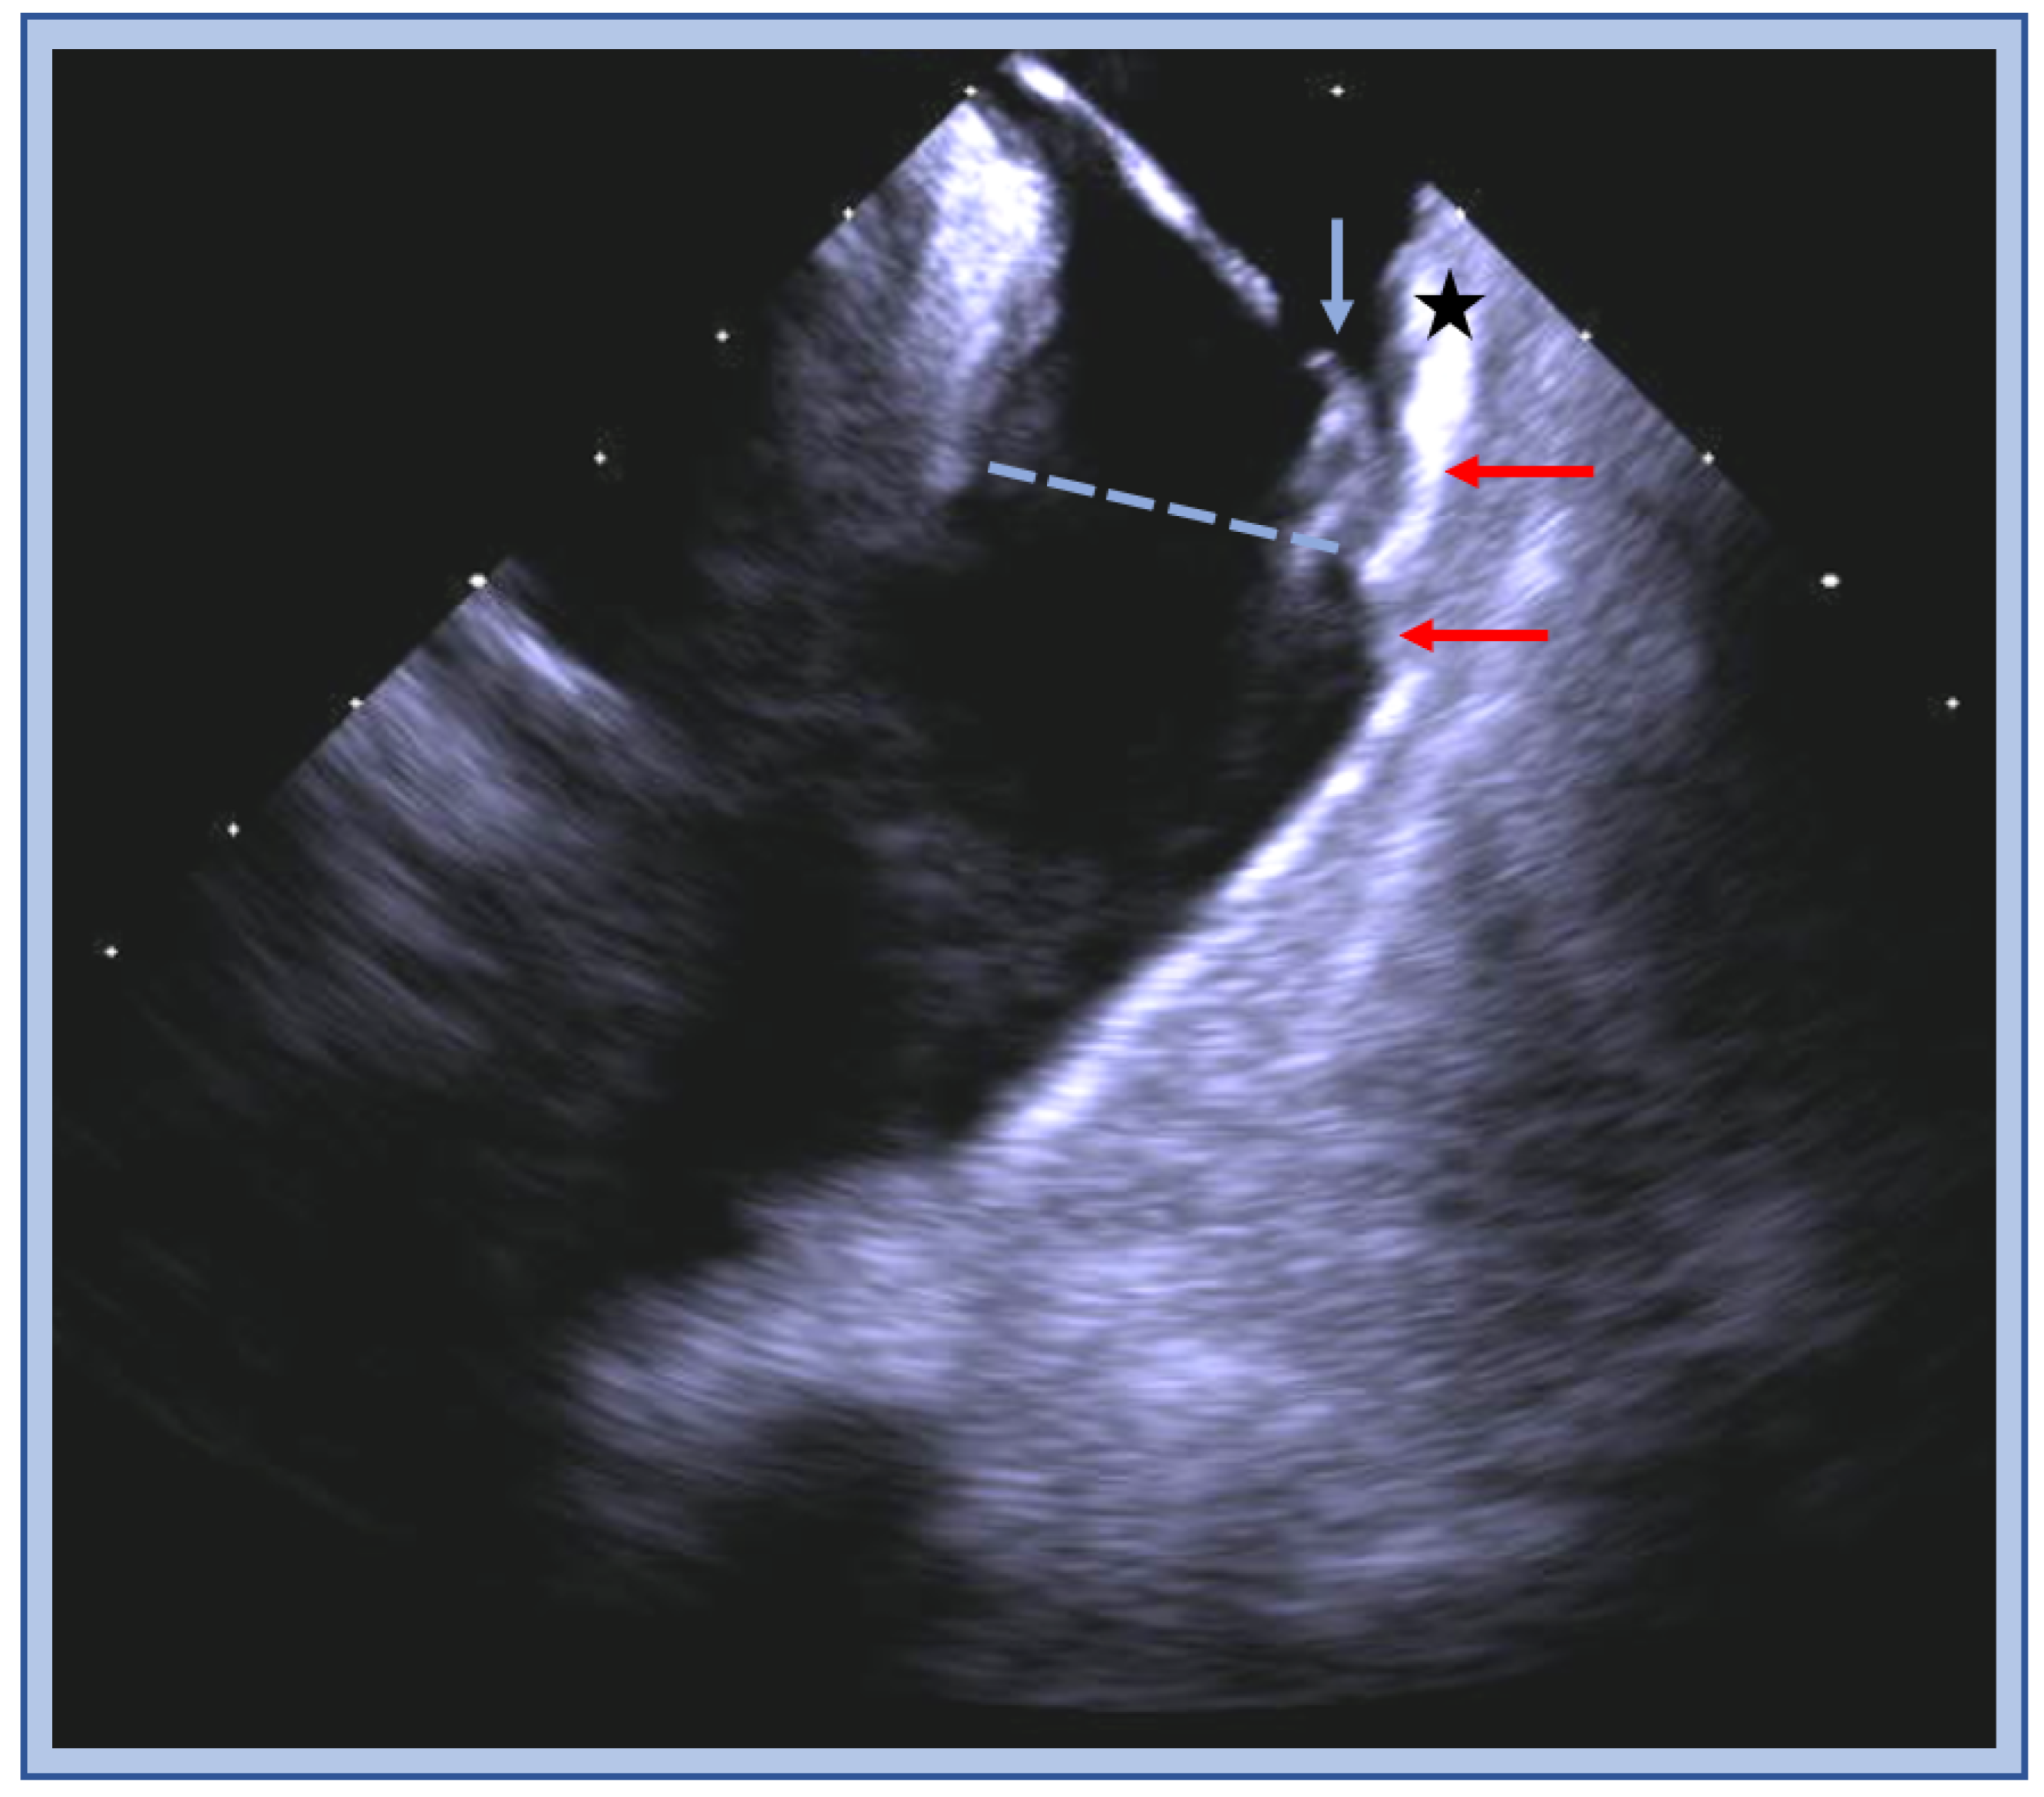

| Papillary Muscle VT Ablation Tips |

|---|

|